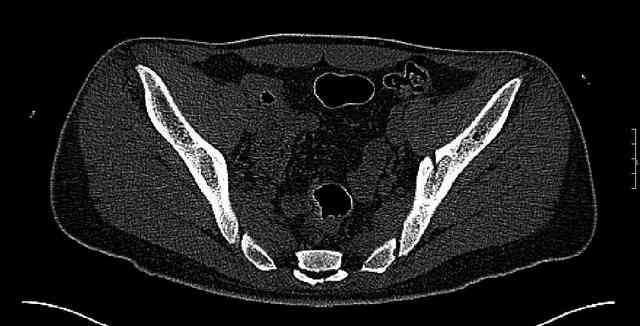

Some more images. Does it help to guess which part of the acetabulum is displaced?